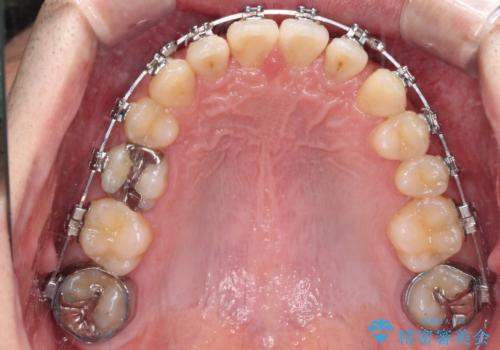

- 矯正装置

- メタルブラケット

奥歯は手前に倒れてしまっているため、後方に起き上がらせることで深い咬み合わせ・ディープバイトを改善する必要があります。

ディープバイトの方は項合力が強大であることが特徴のため、仕上がりを重要視して、ワイヤー装置にて矯正治療を行うこととしました。

右上と左下は永久歯が欠如しており、大きさの大きく異なる乳歯が残存していたため、奥歯の咬み合わせを構築するために苦労しました。